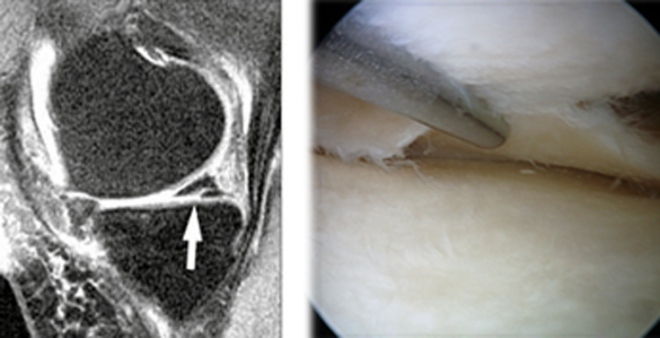

Στους αθλητές που η διάγνωση επιβεβαιώνεται με Μαγνητική Τομογραφία, η θεραπεία είναι χειρουργική (αρθροσκόπηση και μερική μηνισκεκτομή ή συρραφή του μηνίσκου). Όταν η βλάβη είναι μερική, μπορεί κανείς να δοκιμάσει συντηρητική θεραπεία με κηδεμόνα προοδευτικής αλλαγής γωνίας, ασκήσεις τετρακεφάλου και έγχυση αυξητικών παραγόντων (G.F.) από PRP.

Στους μεσήλικες-υπερήλικες η ένδειξη αρθροσκοπικής μηνισκεκτομής είναι πολύ περιορισμένη. Πρέπει εκτός από την μαγνητική τομογραφία να ελεγχθεί και ο άξονας του γόνατος σε ακτινογραφία Face, σε όρθια στάση.

Σε περιπτώσεις που ο ερρηγμένος μηνίσκος έχει αναδιπλωθεί και δεν επιτρέπει την κάμψη ή την έκταση του γόνατος, τότε η εγχείρηση (αρθροσκόπηση) για αφαίρεση του κομμένου μηνίσκου που έχει αναδιπλωθεί (δίκην χειρολαβής κάδου) είναι απαραίτητη.